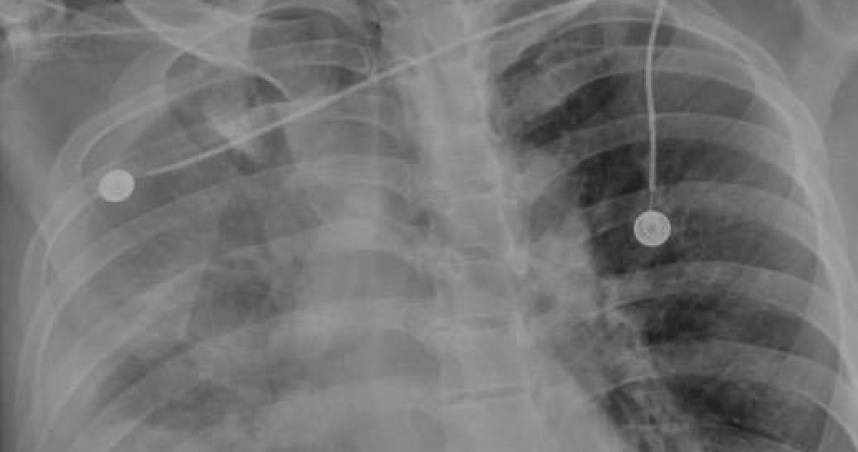

苗栗市2日發生隨機砍人案,48歲邱姓男子持刀攻擊路人,造成2名女童及1名林姓男子多處穿刺傷,隨即分別送至衛福部苗栗醫院、大千綜合醫院救治,所幸目前狀況穩定。對此,苗栗大千醫院外科部長馮啟彥指出,林男緊急被救護車送至急診室後,不僅觀察到其肺臟破裂引發氣血胸,更因為利刃穿刺很深,橫膈膜及肝臟都有破裂及大量出血現象。他也不解直呼,「是有怎樣的深仇大恨?」

曾依殺人未遂罪、傷害罪入監9年才剛出獄的邱男,於10月2日下午戴著安全帽、手上綁著刀具,先後刺傷了2名11歲女童、1名50多歲林姓男子。其中1名女童胸前留下長度約0.5至1公分的割傷,右手肘也有約3公分的切割傷;另1名女童左胸有3至4公分的刺入傷,有明顯血胸、氣胸狀況,插管後轉送中國醫藥大學附設醫院治療;而林男右上腹及背部受穿刺傷、失血過多,在大千醫院加護病房密切觀察治療。

大千醫院外科部長馮啟彥就在臉書發文透露,當時去急診看林男時,「真的是傻眼,是怎樣的深仇大恨?胸、腹、背部都被利刃刺出很大又很深的傷口,本來以為只有氣血胸,但是置放胸管後,仍有持續性出血現象,所以到晚上,我們決定由胸腔外科及一般外科醫師聯手一起介入手術!」

而在手術過程中,馮啟彥表示,不僅發現肺臟破裂引發氣血胸,而且因為利刃穿刺很深,橫膈膜及肝臟都有破裂及大量出血現象。所幸經過手術之後,病情已經比較穩定,3日上午林男雖然仍插著呼吸器,但已經能夠清醒的與大家致意。